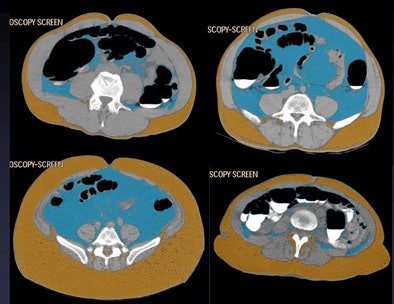

![]() |

| Histogram-based fat assessment software distinguishes abdominal visceral fat (blue) from subcutaneous fat (brown). |

| Four patients show different abdominal fat distribution patterns. |